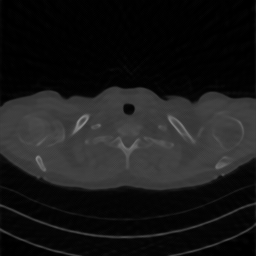

A qualitative comparison can be carried out by examining Figures 2, 3, and 4, which show the reconstructions with the zoomed region identified by the red square. The figures confirm the results reported in the tables, as the reconstructions obtained with DPS and DiffPIR contain noticeable errors. In particular, the DiffPIR reconstruction appears highly blurred and poorly defined. With respect to the images obtained using the two best-performing methods reported in the table, namely DDRM and RD-DGP, we observe that the resulting images exhibit different characteristics. In particular, the reconstructions of image C081-35 (Figure 2) appear quite similar for both methods, In contrast, for images C081-45 and C081-79, inspection of the cropped regions shown in the figures reveals that the DDRM reconstruction exhibits incorrect object shapes, whereas this effect is substantially less pronounced in the RD-DGP reconstruction. Additionally, DDRM images appear more contrasted but also noisier.

Figure 3: Visual comparison of different reconstruction methods for Sample C081-45 across three sparse-view configurations (nα=30,45,60n_{\alpha}=30,45,60). The red box indicates the zoomed region shown in the inset.